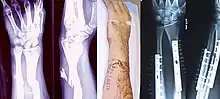

- Distal radius fracture

- Galeazzi fracture – a fracture of the radius with dislocation of the distal radioulnar joint

- Colles' fracture – a distal fracture of the radius with dorsal (posterior) displacement of the wrist and hand

- Smith's fracture – a distal fracture of the radius with volar (ventral) displacement of the wrist and hand

- Barton's fracture – an intra-articular fracture of the distal radius with dislocation of the radiocarpal joint